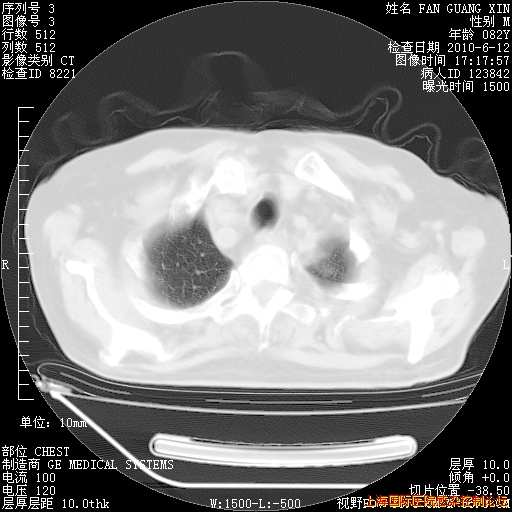

6月12日纵膈窗

整整相隔30天的肺部CT好像有所好转啊。甲强龙减量第3天,需要观察体温。

海管,自昨日你和我通完话后,不知您岳父消化道症状有无缓解?体温怎样?阅读7.12日胸部ct,个人认为目前激素治疗是有效的,甲强龙减量是适宜的。因在抗痨治疗,需密切观察肝功、肾功能和血常规。不过,老年、长期住院和大量使用激素,很担心菌群失调发生